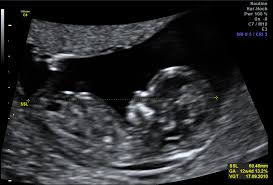

Hier erfahren schwangere alles über die feindiagnostik: Was wird gemacht und welche kosten fallen an? Was passiert bei der feindiagnostik? Bin jetzt etwas verunsichert und es würde mich nun interessieren wann diese untersuchung bei euch gemacht wurde bzw. In solchen fällen wird häufig eine feindiagnostik angeraten. Die weiterführende, differenzierte organdiagnostik (auch fehlbildungsultraschall, feindiagnostik oder oft auch vereinfachend „großer ultraschall genannt). Der altersdurchschnitt der werdenden mütter steigt. Wann sollte das organscreening gemacht werden? Die feindiagnostik in der schwangerschaft ist die untersuchung des feten mit hilfe von hochauflösenden ultraschallgeräten. Ab wann ist diese feindiagnostik eigentlich möglich? Dann sind sie bei dres. Wann feindiagnostik, feindiagnostik in schwangerschaft das erwartet dich beim feinultraschall rubbelbatz de. Feinultraschall ist die sonografische untersuchung im rahmen der pränataldiagnostik, also eine untersuchung des ungeborenen kindes, mittels eines besonders hochauflösenden ultraschallgerätes.

Wann ist der beste zeitpunkt in der schwangerschaft? Ab 40 jahren spricht von einer risikogeburt. Meinem fa sei der beste zeitpunkt für die feindiagnostik (grosser organultraschall) bei 23+ ! Wann ein organscreening gemacht wird. Was wird da genau gemacht? Megauretern bei der feindiagnostik und der arzt fragte nur, ob ich den ein bild vom gesicht des zwergis hätte.und da wurde halt mehr durch zufall festgestellt. Wann ist das sinnvoll und wer trägt die kosten für dafür? Was passiert bei der feindiagnostik? Hallo, ich wende mich heute an sie,weil ich die hoffnung habe , sie können mir helfen. Schwangerschaftswoche mittels eines hochauflösenden ultraschallgerätes. Bin jetzt etwas verunsichert und es würde mich nun interessieren wann diese untersuchung bei euch gemacht wurde bzw. Der altersdurchschnitt der werdenden mütter steigt. Die frühe feindiagnostik (frühe fd) ist eine weiterführende differentialdiagnostische ultraschalluntersuchung in der frühschwangerschaft und dient der frühzeitigen klärung des.

Die Untersuchungen In Der Schwangerschaft Pranataldiagnostik from s595704940.online.de Wann ist eine fetale herzdiagnostik sinnvoll? Synonym werden die ausdrücke sonografische feindiagnostik. Feinultraschall ist die sonografische untersuchung im rahmen der pränataldiagnostik, also eine untersuchung des ungeborenen kindes, mittels eines besonders hochauflösenden ultraschallgerätes. Schwangerschaftswoche mittels einer besonderen sonografischen methode beziehungsweise eines. Wann kann eine fetale echokardiografie durchgeführt werden? Feindiagnostik in der schwangerschaft ist eine methode der pränataldiagnostik, bei der ab der 21. Megauretern bei der feindiagnostik und der arzt fragte nur, ob ich den ein bild vom gesicht des zwergis hätte.und da wurde halt mehr durch zufall festgestellt. Ab wann kann man die feindiagnostik machen.